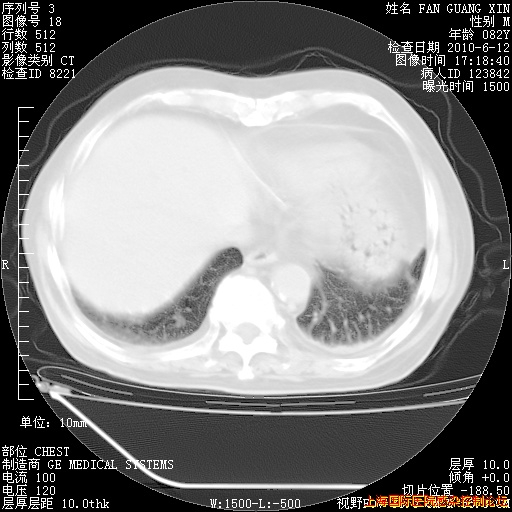

6月12日肺窗

6月12日纵膈窗